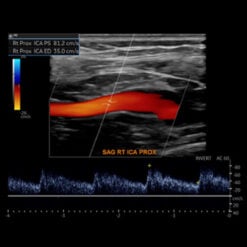

- Peripheral Vascular Emergencies – Claire Sandstrom, MD

- Blunt Cerebrovascular Injury – Jason Hartman, MD